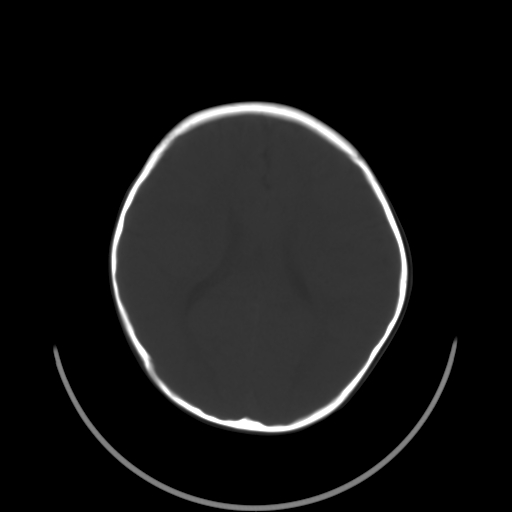

以下是引用深泽交通医院在2009-10-16 8:25:00的发言:[br]右眼环出血伴异物

以下是引用卜一在2009-10-16 15:01:00的发言:[br]右眼球挫裂伤伴异物!

以下是引用拾荒者在2009-10-17 18:38:00的发言:[br]鼻面部皮下积气,右侧睑缘及眼球壁高密度异物影,左侧眼球壁晶状体内侧缘处是圆形低密度影。低密度异物?应提请眼科医生注意。